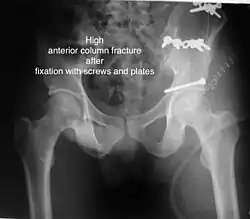

High anterior column fracture after fixation with screws and plates

The final management depends on the size of the fragment(s), stability and congruence of the joint. In some cases traction for six to eight weeks may be the only treatment required; however, surgical fixation using screw(s) and plate(s) may be required if the injury is more complex. The latter treatment will be called for if bone fragments do not fall into place, or if they are found in the joint, or if the joint itself is unstable.